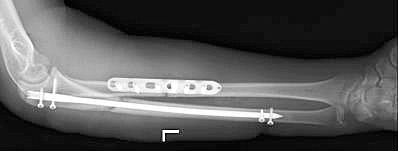

Mai des decât alte fixatori pentru fracturi ale radius și cubitus cu ajutorul plăcii și șuruburi speciale. Osteosinteza raza fracturat și cubitus este „standardul de aur“, în traumatologie.

Plăci moderne și șuruburi permit fixarea fragmentelor de fractură în punctul anatomică corectă de vedere al situației, precum și de mână a avut loc această poziție până când uniunea fractură.

fuziune osoasă diafizare la adult durează o perioadă lungă de timp. După șase săptămâni de pe X-ray puteți vedea primele semne ale calus. După 10 săptămâni, os rezistența fractură în regiunea de până la 80 la sută din original. consolidare completă și restructurare a osului poate dura până la câțiva ani. Odată ce fractura a crescut împreună, ne putem gândi la eliminarea metallofiksatora, deși acest lucru este opțională. În unele cazuri, mettalofiksator poate provoca disconfort, un sentiment de tandrețe. De obicei, tije și plăci ale radius și cubitus oasele sunt eliminate nu mai devreme de 2 ani, cu condiția ca semne radiologice de consolidare fracturii.